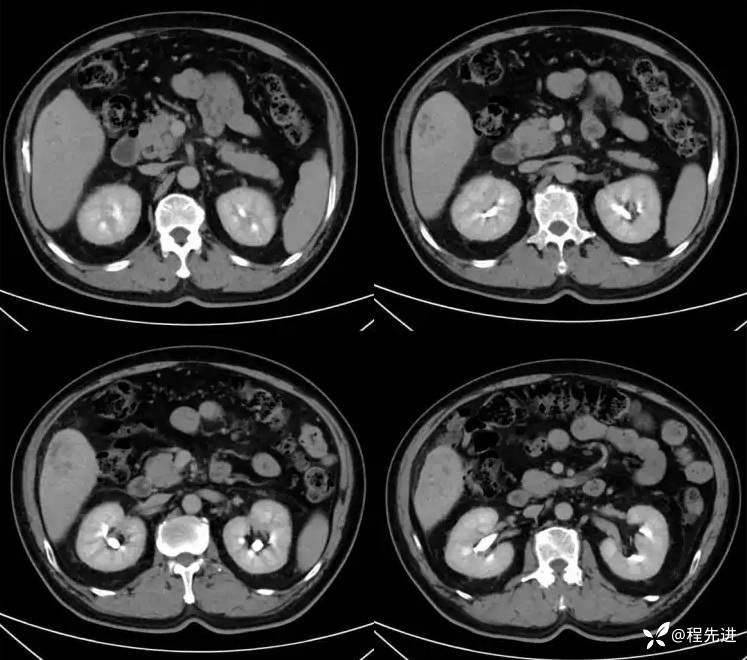

T2:

DWI、ADC

T1蒙片:

动脉期:

门静脉期: